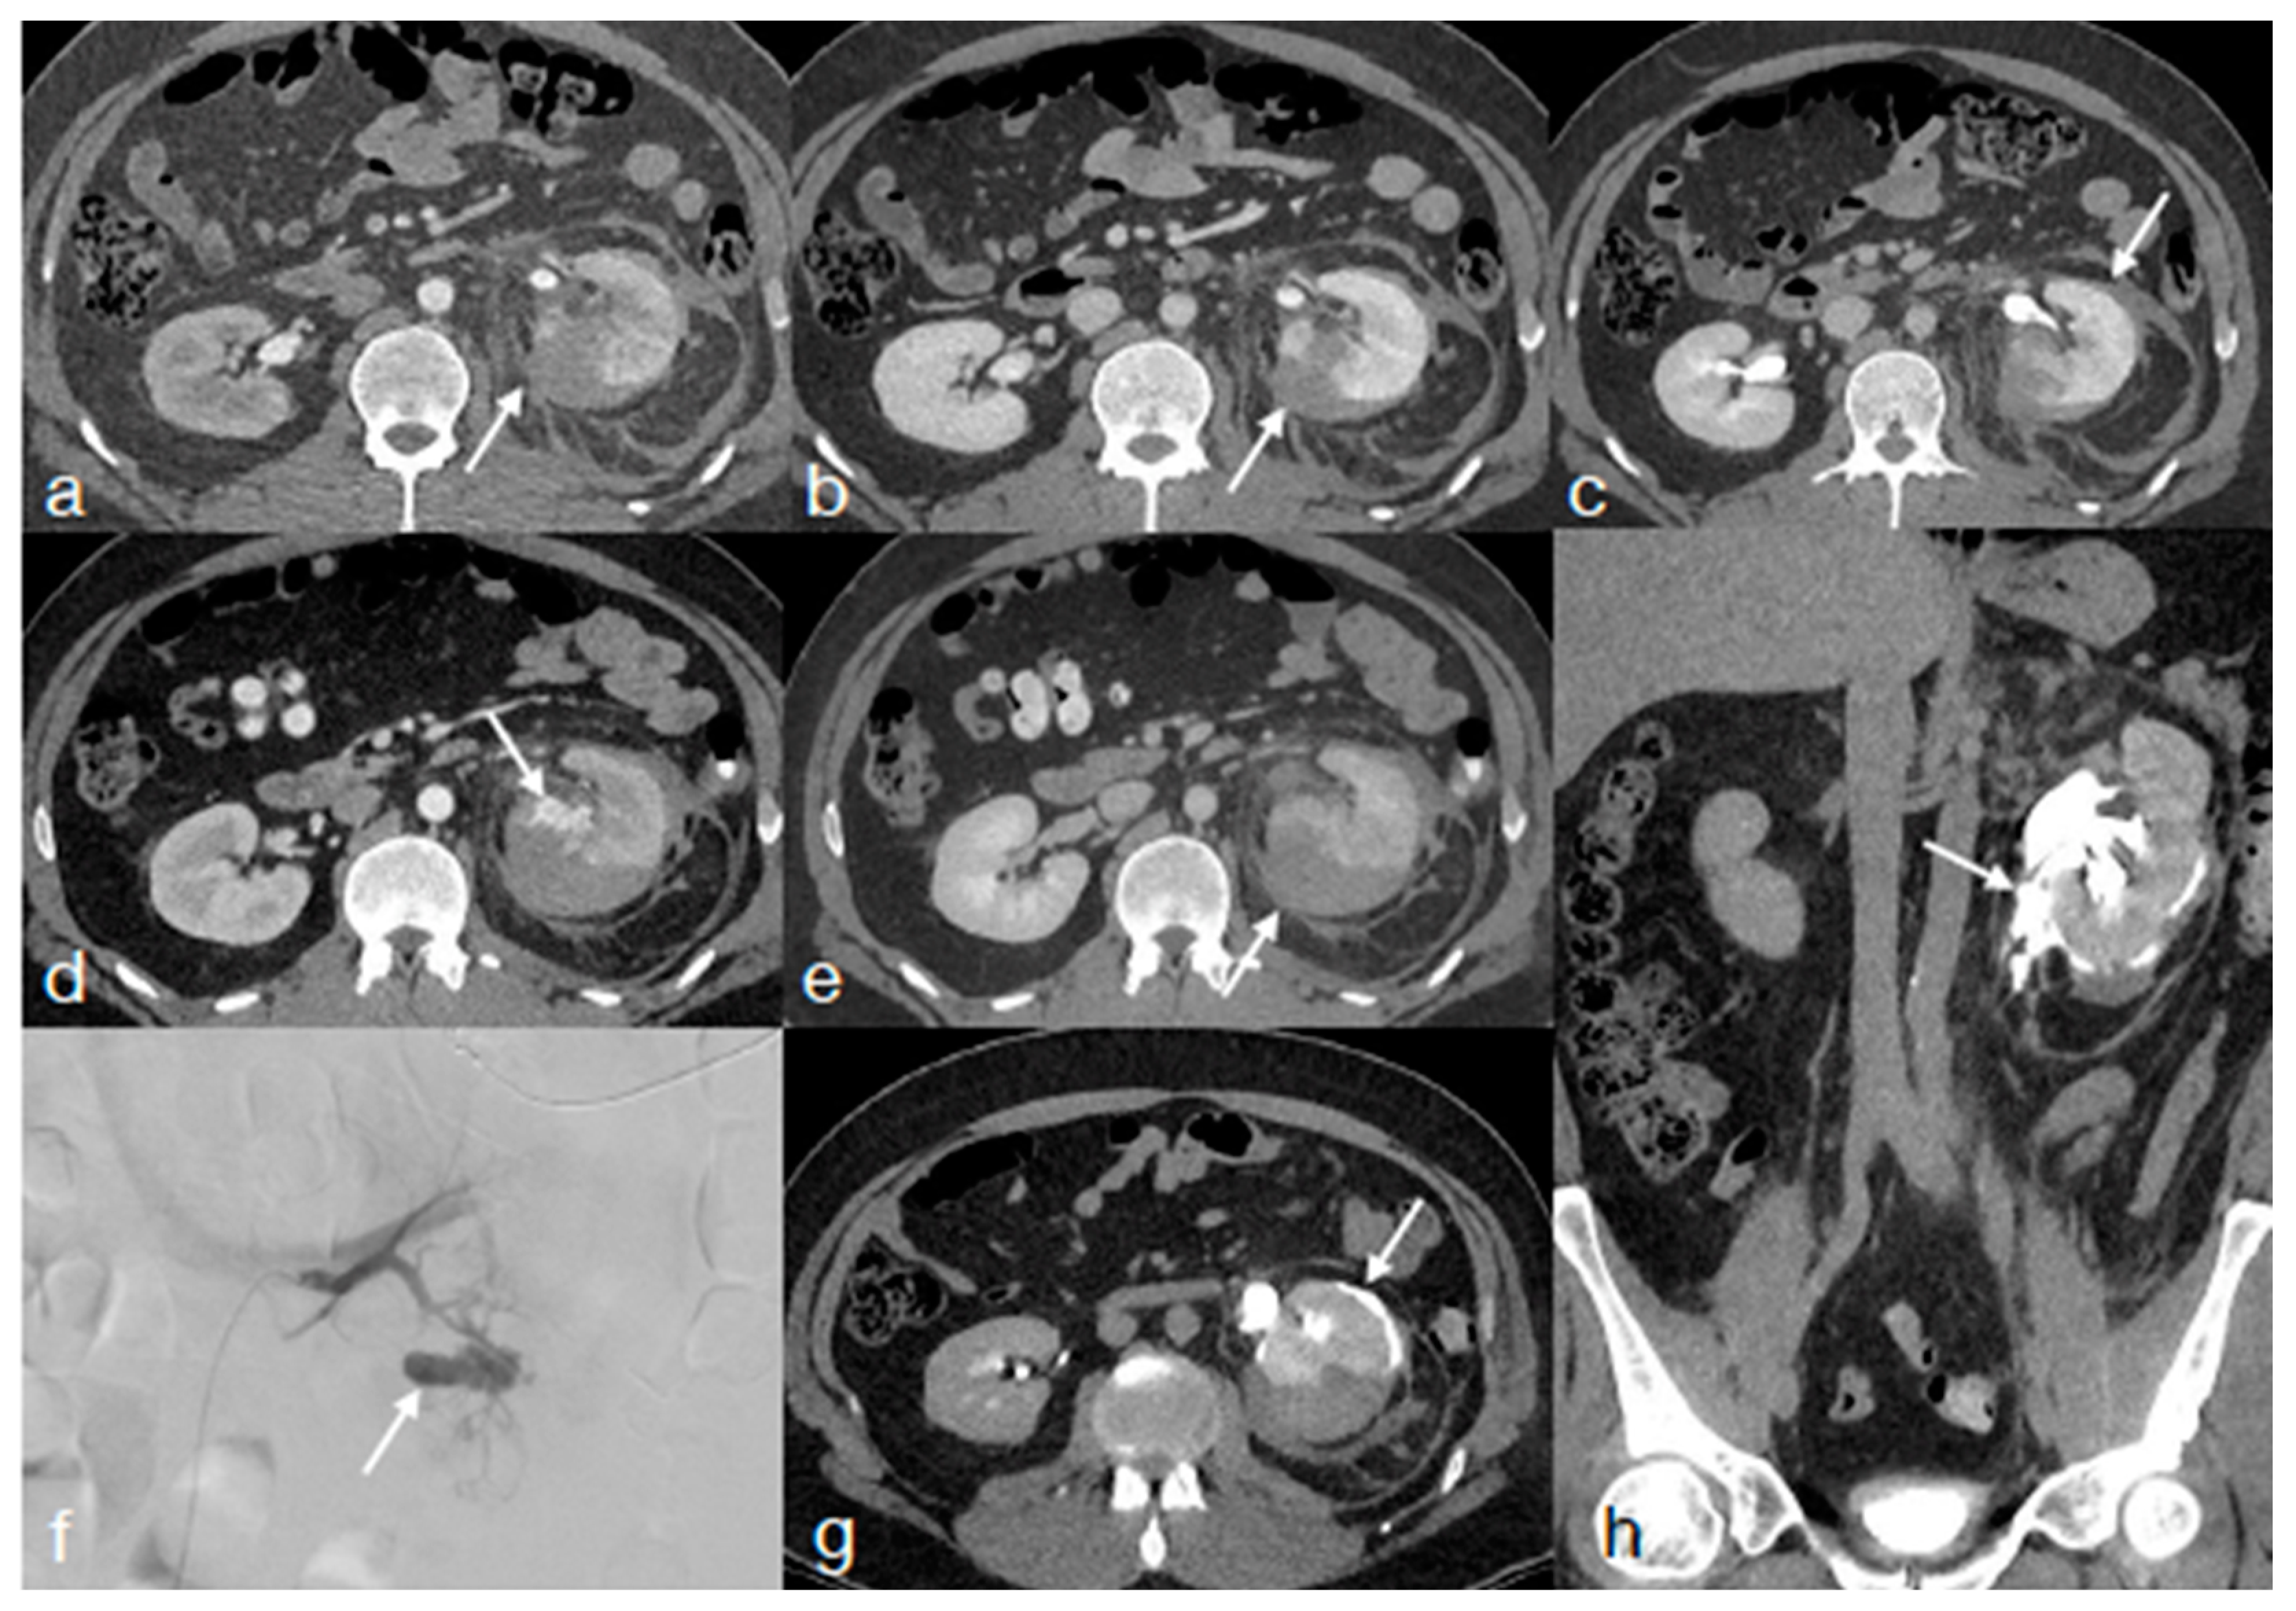

- Di Serafino, M.; Iacobellis, F.; Schillirò, M.L.; Ronza, R.; Verde, F.; Grimaldi, D.; Dell’Aversano Orabona, G.; Caruso, M.; Sabatino, V.; Rinaldo, C.; et al. The Technique and Advantages of Contrast-Enhanced Ultrasound in the Diagnosis and Follow-Up of Traumatic Abdomen Solid Organ Injuries. Diagnostics 2022, 12, 435. [Google Scholar] [CrossRef] [PubMed]

- Iacobellis, F.; Iacobellis, F.; Scaglione, M.; Scaglione, M.; Brillantino, A.; Brillantino, A.; Scuderi, M.G.; Scuderi, M.G.; Giurazza, F.; Giurazza, F.; et al. The additional value of the arterial phase in the CT assessment of liver vascular injuries after high-energy blunt trauma. Emerg. Radiol. 2019, 26, 647–654. [Google Scholar] [CrossRef]

- Uyeda, J.W.; LeBedis, C.A.; Penn, D.R.; Soto, J.A.; Anderson, S.W. Active Hemorrhage and Vascular Injuries in Splenic Trauma: Utility of the Arterial Phase in Multidetector CT. Radiology 2014, 270, 99–106. [Google Scholar] [CrossRef] [PubMed]